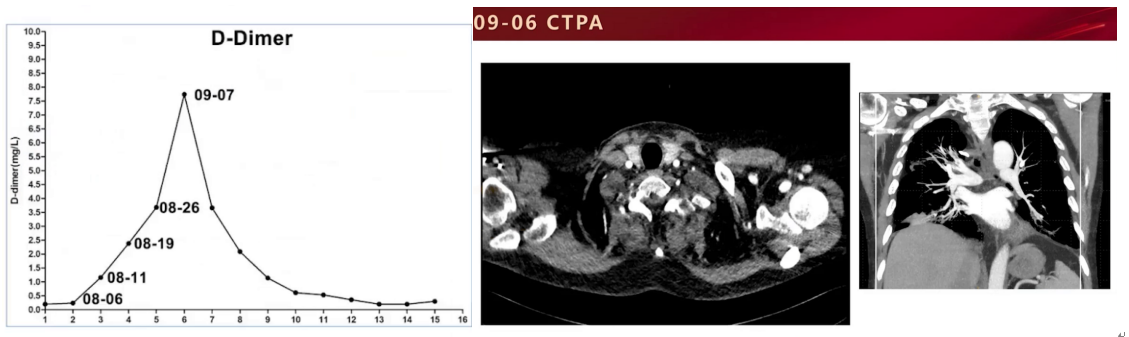

入科时,患者生命体征尚可,脉搏和呼吸频率偏快,经鼻高流量湿化氧疗,吸氧浓度需求高,动脉血气提示中度呼吸衰竭和过度通气,心电图提示窦性心动过速。回顾前期检查发现患者D-二聚体持续升高,9月6日转科后即行CTPA检查,虽动脉期和静脉期区分不佳,但仍可见右肺上叶、右肺下叶及左肺下叶多发肺动脉充盈缺损,右肺上叶病变强化明显减低,右下叶和左下叶病灶有明显强化区域,提示病变性质可能存在差异,调整诊断为肺栓塞。

治疗上停用抗生素,恢复原糖皮质激素联合免疫抑制剂抗排斥治疗,加用利伐沙班15mg Q12h口服抗凝治疗,并对肺栓塞严重程度及病因进行筛查,结果显示心肌酶基本正常,四肢超声未见深静脉血栓形成,睡眠呼吸监测仅有轻度睡眠呼吸暂停低通气综合征,拔除深静脉导管未见肉眼栓塞。抗凝及抗血小板治疗后,患者氧合指数无明显改善,但吸氧浓度需求逐渐下降,过度通气情况好转,主观症状逐步改善。

9月29日复查胸部CTPA,两肺病灶总体呈吸收状态,但左下叶未好转且体积进一步缩小。